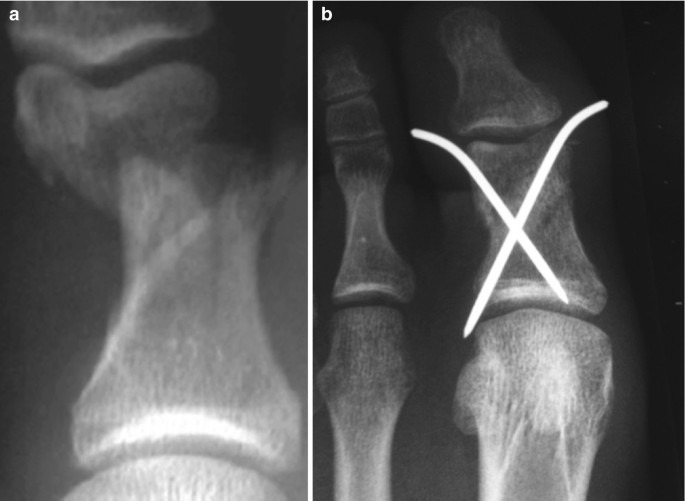

병원에서는 우선 X-ray 촬영을 통해 뼈의 어긋남 여부를 확인한다. 단순 골절이라면 부목 고정이나 깁스로 충분하지만, 뼈가 틀어졌거나 조각난 경우에는 정복술 또는 핀 고정 수술이 필요하다. 치료 과정은 다음과 같이 진행된다.

- 수술: 금속 핀, 나사, 철심을 이용한 내고정술 시행(개방성·분쇄성 골절 등)